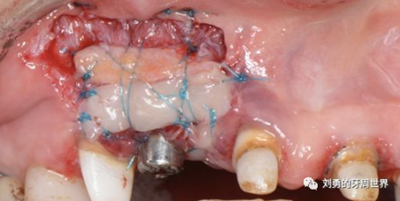

該方式齦瓣固定的效果差,術(shù)后血供差,為了改善血供,我們提倡下面的改良縫合方式,血供更好,成功率更高,如下圖:

通過用縫線壓迫的方式固定,術(shù)后愈合的過程齦瓣始終與受區(qū)骨膜貼合,而不會移動。

但是該方法對于縫合技術(shù)要求較高,因此本人嘗試了新的方法,膜釘固定:

該方法操作簡單,但是需要擇期局麻下拆除膜釘。

國外還有一種更加簡便的方法,使用生物膠粘接固定,如下圖: